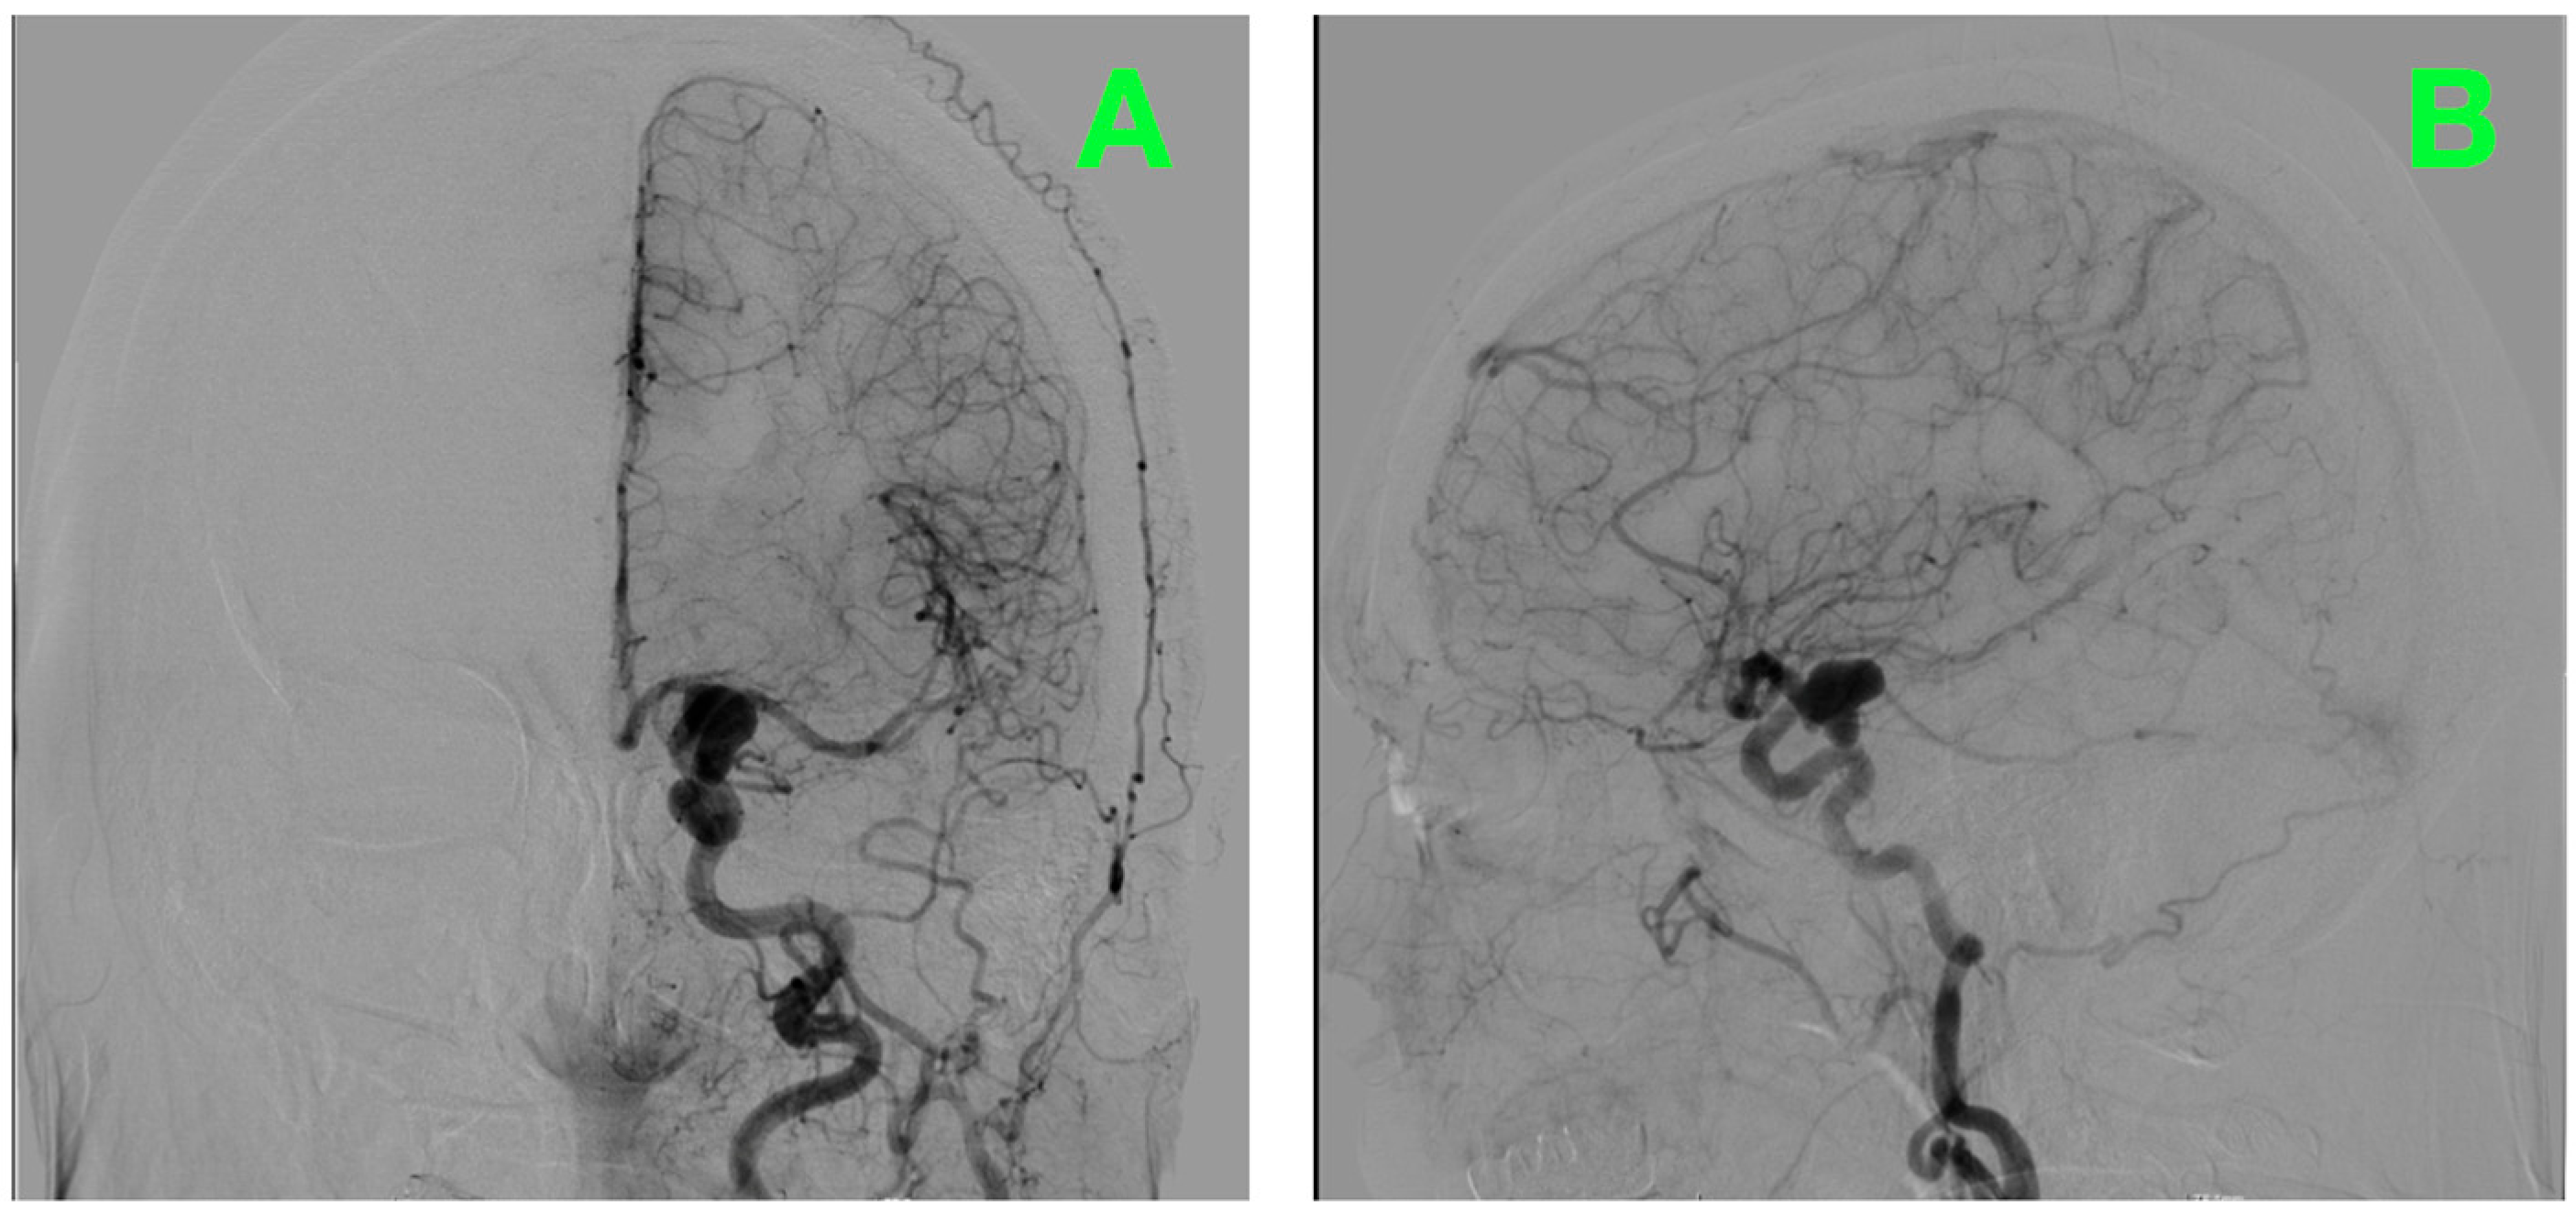

2.6. Preoperative Angiographic Findings